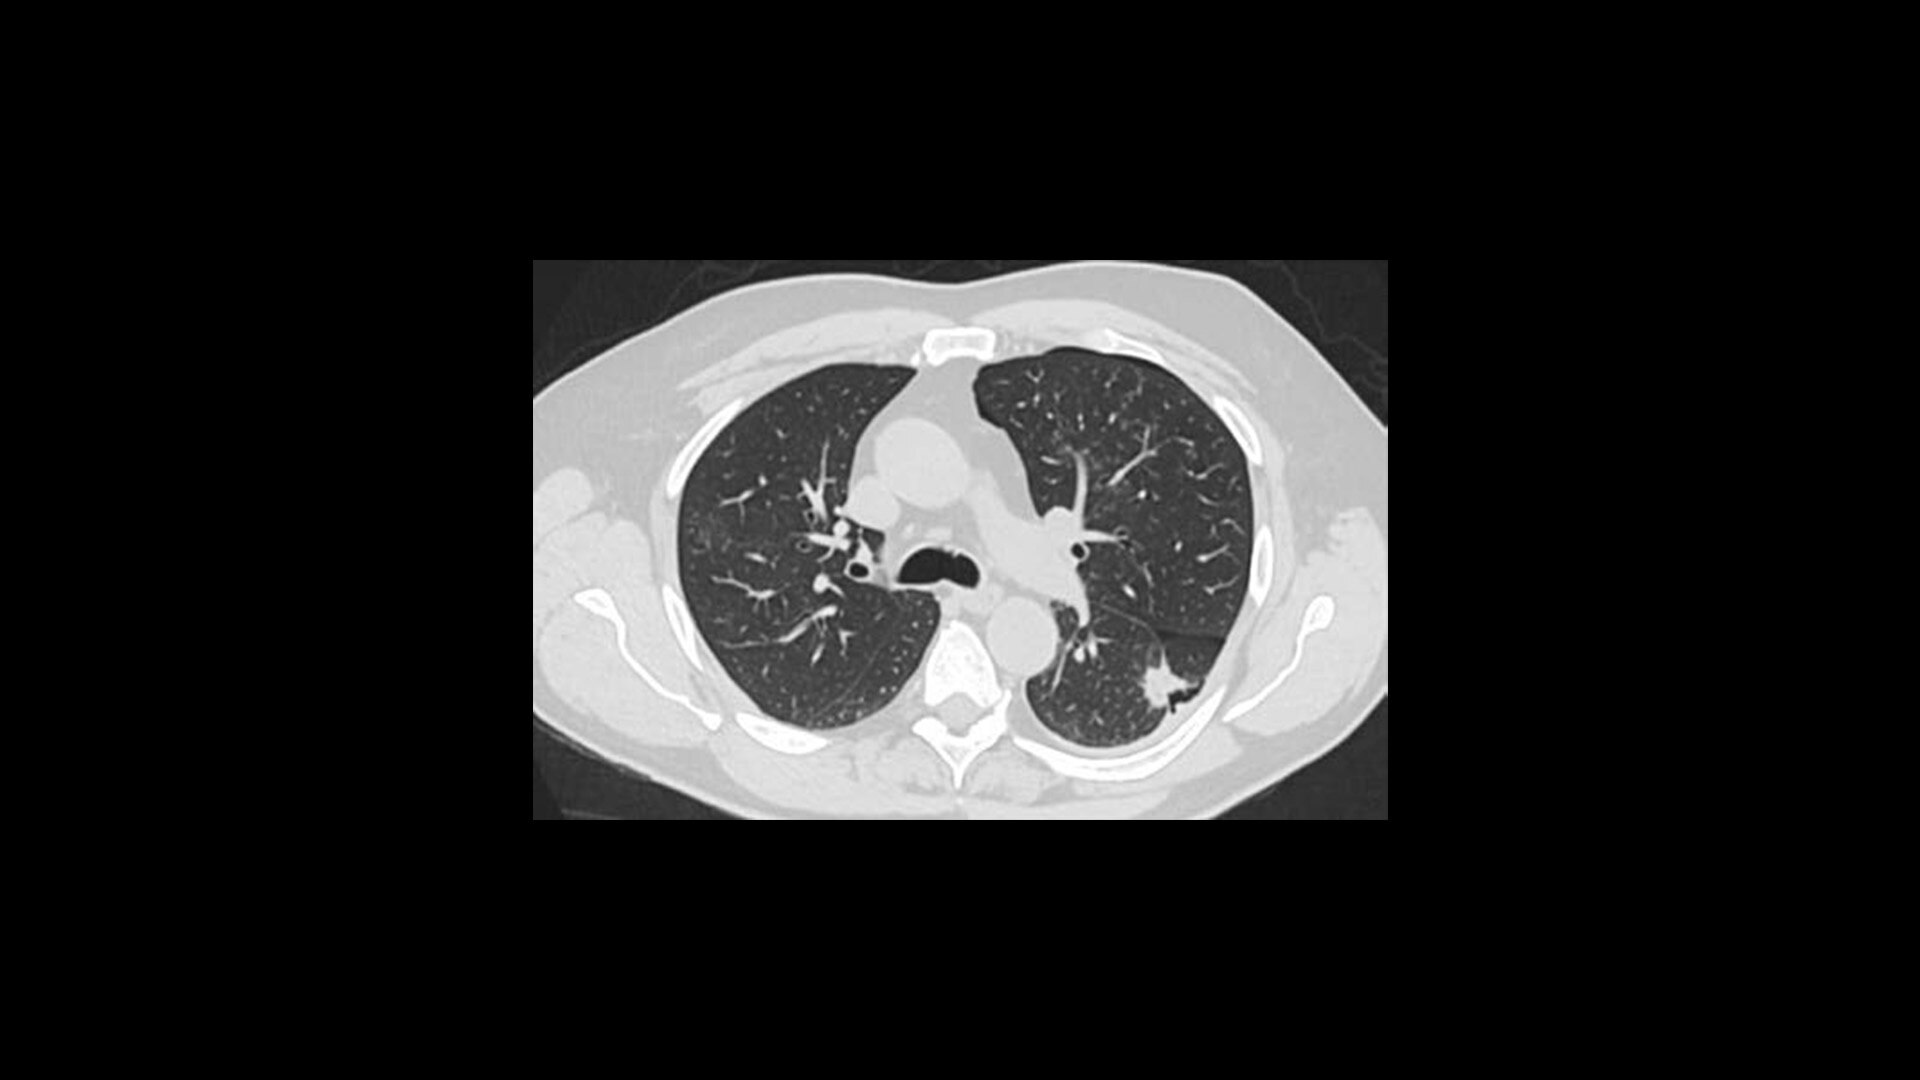

TrueFidelity DL

Deep learning for a deeper understanding

TrueFidelity™ DL is our state-of-the-art image reconstruction technology that uses a DNN to generate high-definition, low-noise CT images. It produces images with exceptional sharpness, low-contrast image quality performance and your preferred noise texture, at the same dose.¹